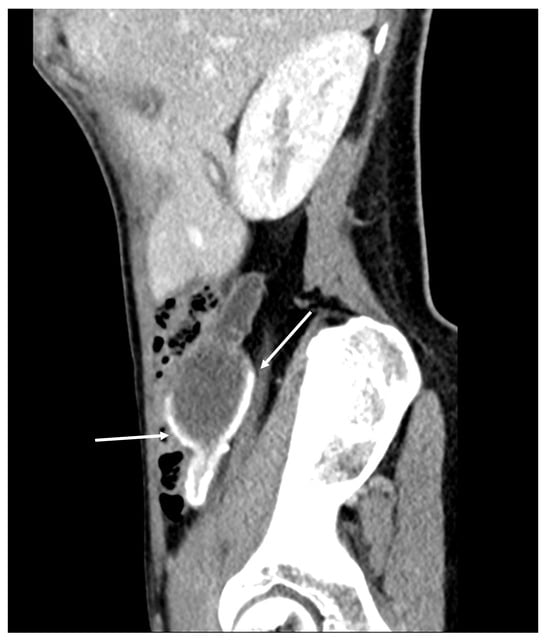

Figure 20. Recurrence four years after CRS + HIPEC. Mucinous tumor around the liver and in the porta hepatis (arrows). This patient was successfully treated with repeated CRS + HIPEC. (CT, portal phase, coronar plane).

Patients who have undergone cytoreductive surgery and HIPEC due to pseudomyxoma peritonei should be followed up with imaging studies at regular intervals. Recurrence may occur after several years (Figure 20 and Figure 21).